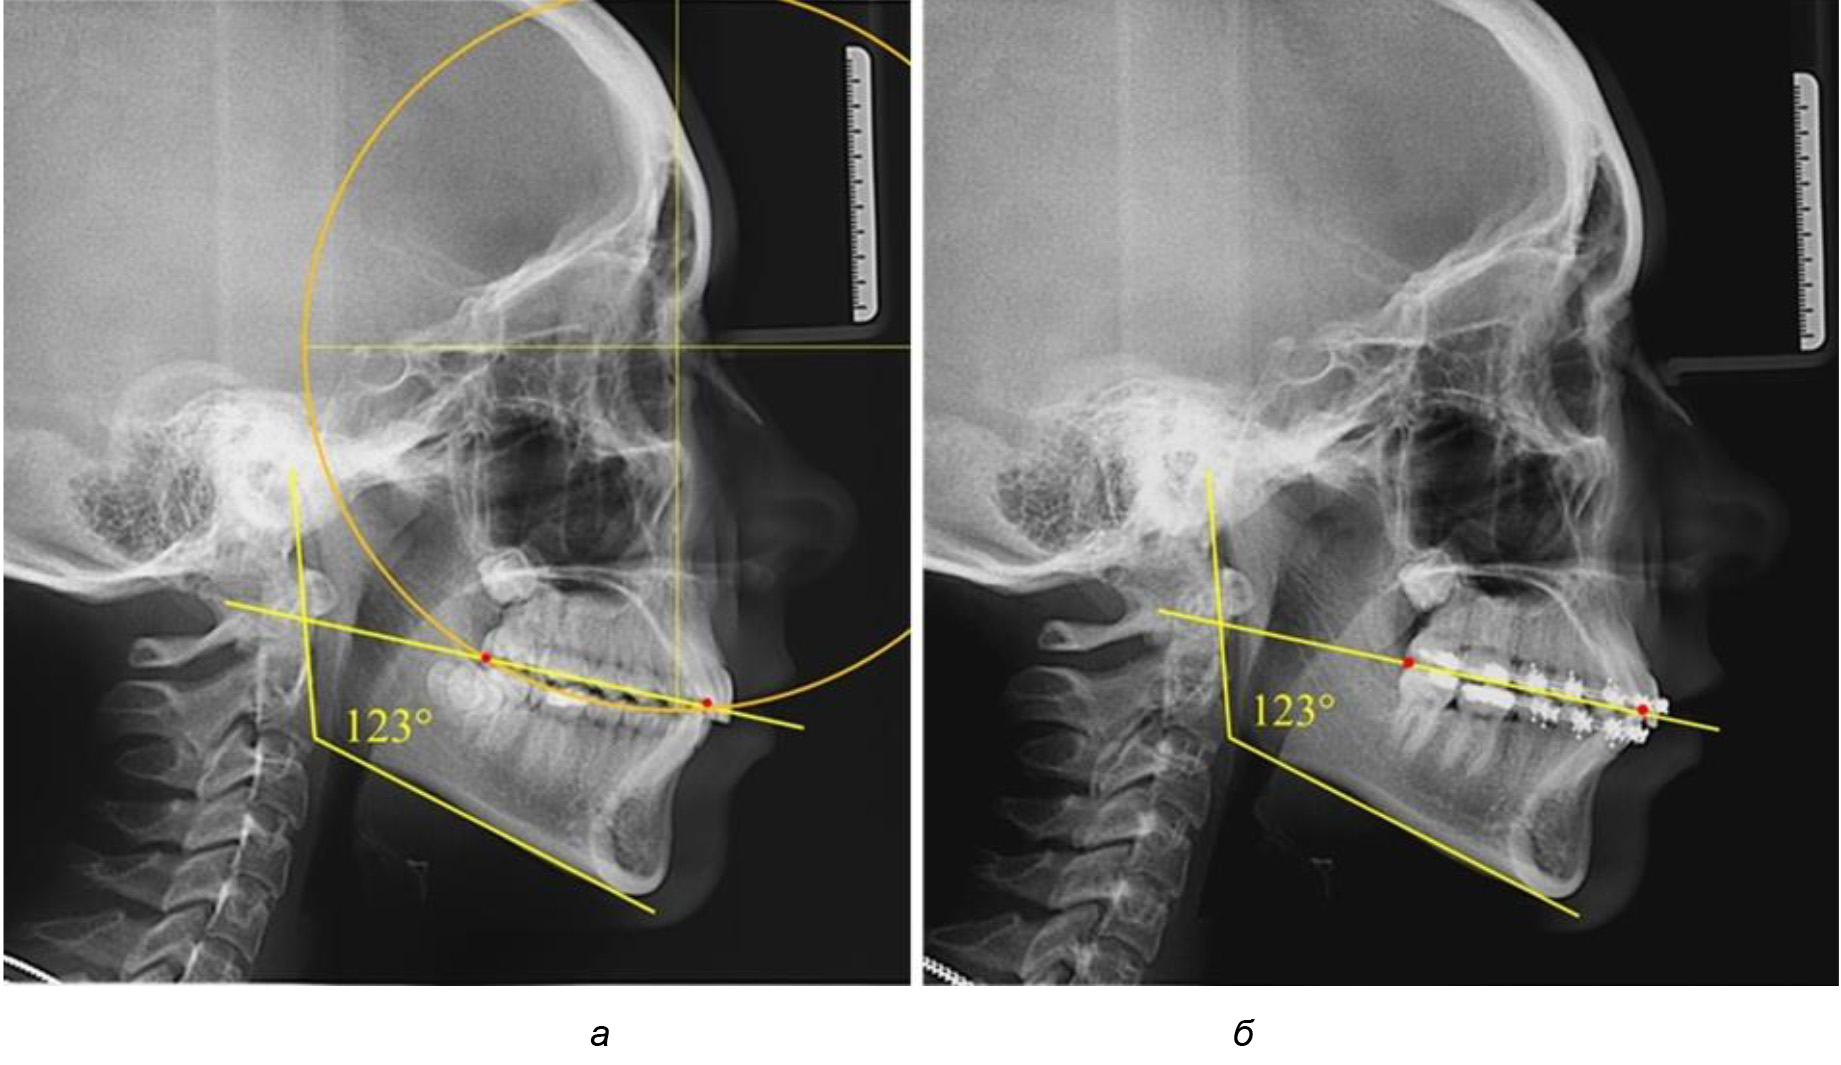

Рис. 1. Метод определения кривой Spee на ТРГ (а) и на ОПТГ (б)

Деление величины радиуса круга к длине окклюзионной линии составило 1,623 ± 0,02. Таким образом, для определения радиуса окружности, соответствующей кривизне окклюзионного контура боковой ТРГ, необходимо измерить расстояние между передней и задней окклюзионными точками и последующим умножением полученной величины на число Фибоначчи (рис. 2).

Рис. 2. Особенности кривой Spee на ТРГ (а) и ОПТГ (б) у людей с признаками вертикального роста